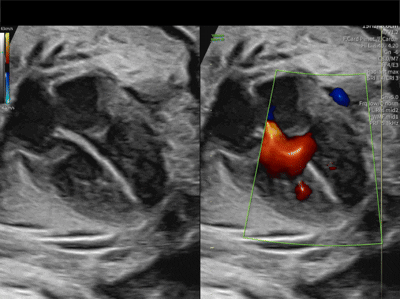

What defect is shown?

What direction is the flow?

What is a bidirectional VSD